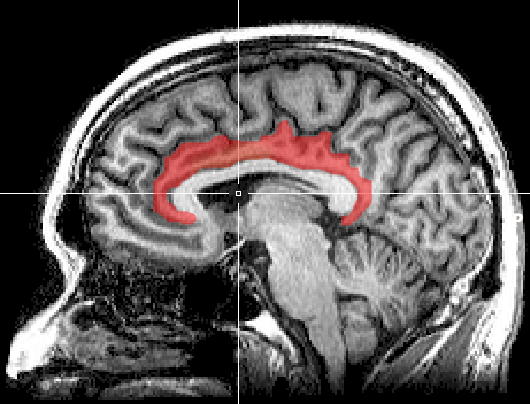

默认模式网络(default mode network)活动的降低是大脑在集中注意力时最明显的信号。默认模式网络主要由内侧前额叶皮质,后扣带回皮质和角形脑回(angular gyrus)组成,是一个横跨整个大脑的大型神经网络。在人们无事可做、胡思乱想的时候,默认模式网络会变得非常活跃。同时,它也参与包括环境观测、自我参照、社会认知等其他复杂的认知功能。

图片

大脑默认模式网络的3D模拟图像

Andreashorn